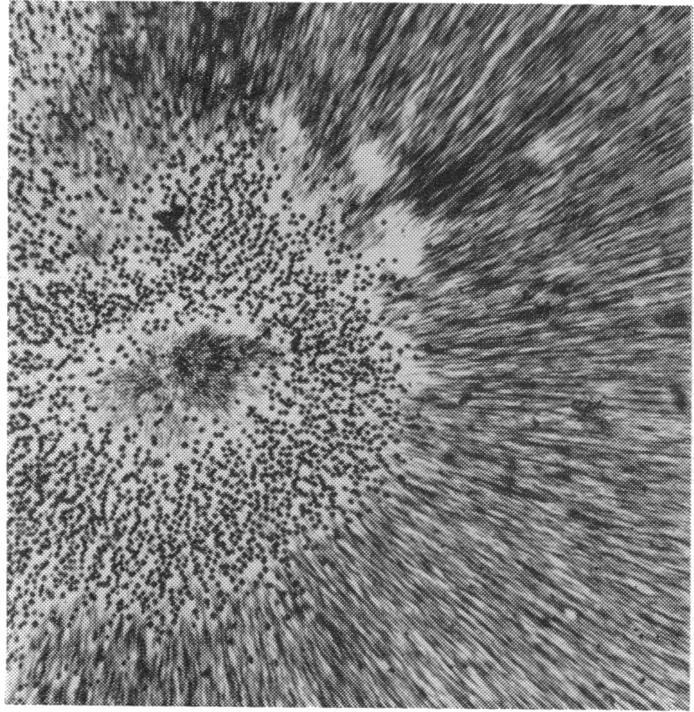

RETINAL PATHOLOGY AFTER CENTRAL RETINAL VEIN OCCLUSION.

Br J Ophthalmol. 1961 Oct;45(10):683-94. doi: 10.1136/bjo.45.10.683.